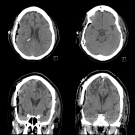

A 54-year-old African American woman with a medical history of type 2 diabetes, hyperlipidemia, iron-deficiency anemia, hypertension, stroke, and seizures presented to a rehabilitation hospital with a...

07/30/2020